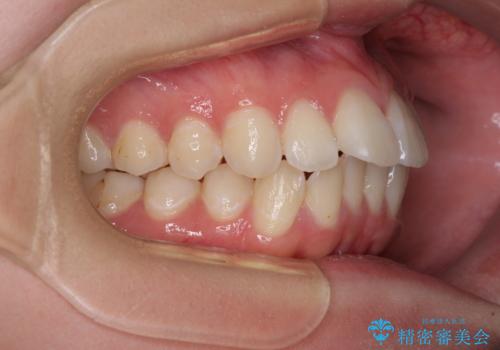

上下前歯の突出感とデコボコを気にして来院された患者様です。

インビザラインによる上下歯列の側方拡大と後方移動、必要に応じてIPR(歯と歯の間を削る)によりスペースの獲得により歯列を整えることとしました。

治療途中、出産や転居があり、2年ほど治療期間が長くなってしまいましたが、前歯の歯並びや飛び出した感覚を無事に改善させることができました。